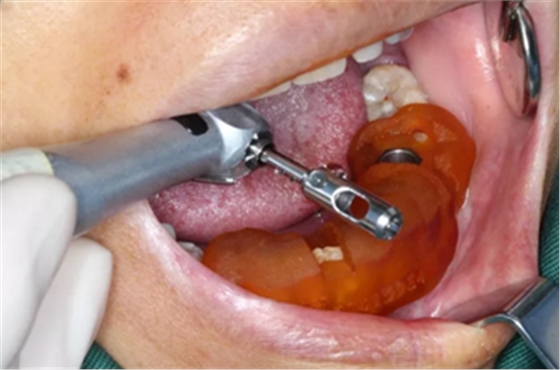

3.根据手术计划书,使用术前所设计好的长度、直径的一系列钻针在导板的引导下进行备孔。

4.在全程导板的引导下,使用全程导板工具盒中的携带器,从导板套环孔处将植体植入,直至携带器的六角、与导板套环的六角严丝合缝(如图,六角对六角),即表示植体就位成功。